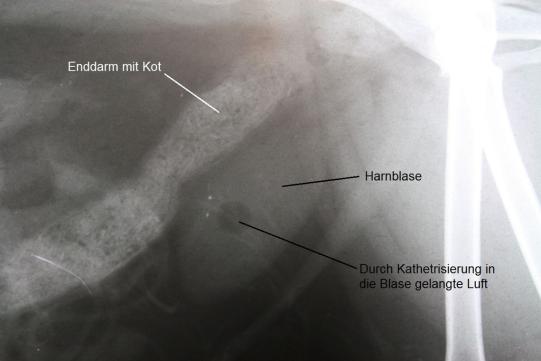

Da Ronja ein weibliches Tier ist, kommt hier eine elegante Methode zur Blasensteinentfernung zur Anwendung: Die Urohydro-Propulsion. Hierbei wird die Blase der Katze unter Narkose mit einem feinen Katheter mit Kochsalzlösung gefüllt. Das Tier wird anschliessend von einer Hilfsperson unter den Vorderbeinen so angehoben, dass die Katze aufrecht in der Luft hängt. Dadurch sammeln sich die Blasensteine im tiefstliegenden Punkt der Blase (dem Blasenhals) und können durch manuelles Auspressen der Blase mitsamt der Kochsalzlösung in die Harnröhre und damit ans Tageslicht befördert werden. Dieser Vorgang wird einige Male wiederholt, bis keine Blasensteine mehr ausgespült werden können. Ein abschliessendes Röntgen bestätigt die komplette Entfernung der mehreren Dutzend Blasensteine.

Blasensteine sind bei älteren Katzen recht häufig zu finden. Je nach Zusammensetzung können die Steine röntgendicht (d.h. "weiss") oder röntgendurchlässig (d.h. "dunkel" und damit im Röntgen nicht erkennbar) sein. Je nach Zusammensetzung kann versucht werden, die Steine mittels Futterwechsel aufzulösen. Da die Blasensteine bei Ronja stark röntgendicht waren, musste davon ausgegangen werden, dass es sich um Calcium-Oxalat-Steine handelte, welche nur mechanisch entfernt werden können. Diese Annahme wurde durch die Untersuchung der Steine nach Entfernung bestätigt.